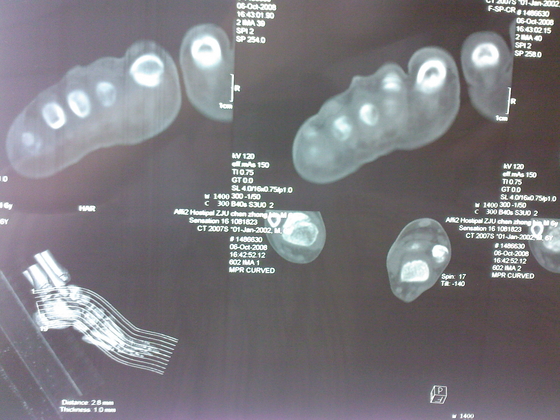

把病理送浙一医会诊后诊断为:骨外软骨瘤。同时做了CT检查。暂未予治疗。

今天把创面情况跟CT发上请大家看看。

继续发CT片

继续还有几张。